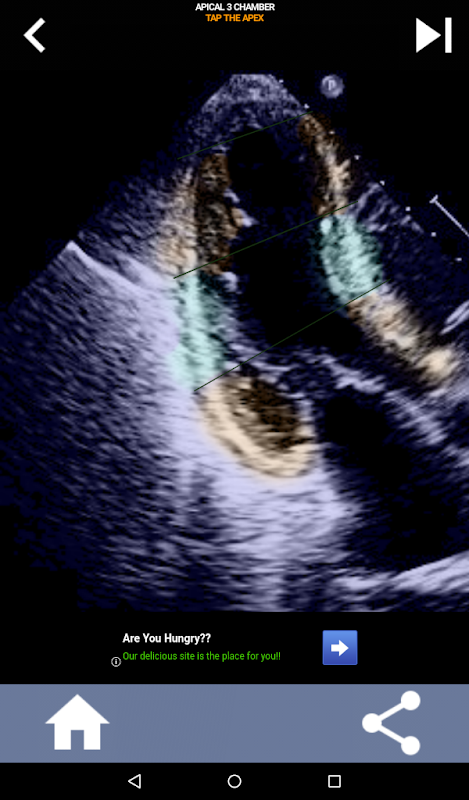

رویکرد بصری مبتنی بر آزمون برای یادگیری بخشهای قلب AHA: اکوکاردیوگرافی

درک بخش های قلب AHA (انجمن قلب آمریکا) برای یک متخصص سونوگرافی قلب برای برقراری ارتباط موثر با متخصص قلب که گزارش را می نویسد بسیار مهم است. با دانستن نواحی آناتومیکی خاص و بخشهای مربوط به آنها، سونوگرافیست میتواند هر گونه ناهنجاری یا یافتهای را بهطور دقیق توصیف کرده و با آن ارتباط برقرار کند و از ارتباط واضح و مختصر بین هر دو متخصص اطمینان حاصل کند.

این درک به ویژه زمانی بسیار مهم می شود که متخصص قلب به دنبال تعیین محل دقیق یک مشکل باشد یا زمانی که پزشک در حال خدمت مشکلی را در یک منطقه خاص شناسایی می کند و سونوگرافیست را وادار می کند تا قسمت مربوطه را به طور دقیق نمایش دهد، مانند دیواره میانی تحتانی. بنابراین، داشتن درک جامع از بخش های قلب AHA مجموعه مهارت های ضروری است.

این برنامه دانش شما را با استفاده از تصاویر پژواک واقعی آزمایش میکند، که اغلب آنها را بهترین روش تدریس میدانم.